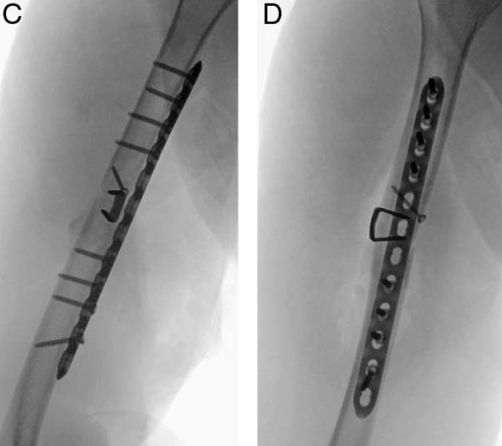

与肱骨干骨折相似,在桡骨干横行骨折的固定中,也可采用骑缝钉临时固定后,再通过钢板螺钉系统确切固定:

【3】Song EY, Emovon EO 3rd, Hollins AW, Saltzman EB, Mithani SK, Richard MJ, Pidgeon TS. The Use of Nitinol Staples as Reduction Aids in Fixation of Forearm Diaphyseal Fractures: Surgical Technique and Case Series. Tech Hand Up Extrem Surg. 2025 Mar 1;29(1):e0496.